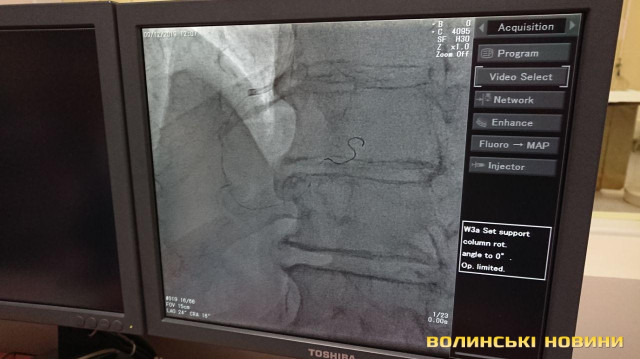

З 2013-го року реперфузійні центри працюють за системою «24/7», тобто ми допомогу надаємо у будь-який час і кожного дня. З 2018 року до цієї роботи долучився реперфузійний центр у м. Ковель завдяки ангіографу, встановленому за кошти субпроекту Світового банку. У нашому центрі щодня маємо 3-5 процедур. Також почали проводити тромбоекстракцію у пацієнтів з ішемічним інсультом. Це складна процедура, яку роблять у небагатьох клініках України. Суть у тому, що при інсульті треба вчасно відкрити судинку. У судину заводиться спеціальне обладнання і проводяться маніпуляції із видалення тромбу. Є випадки, що молодим людям ставало значно краще.